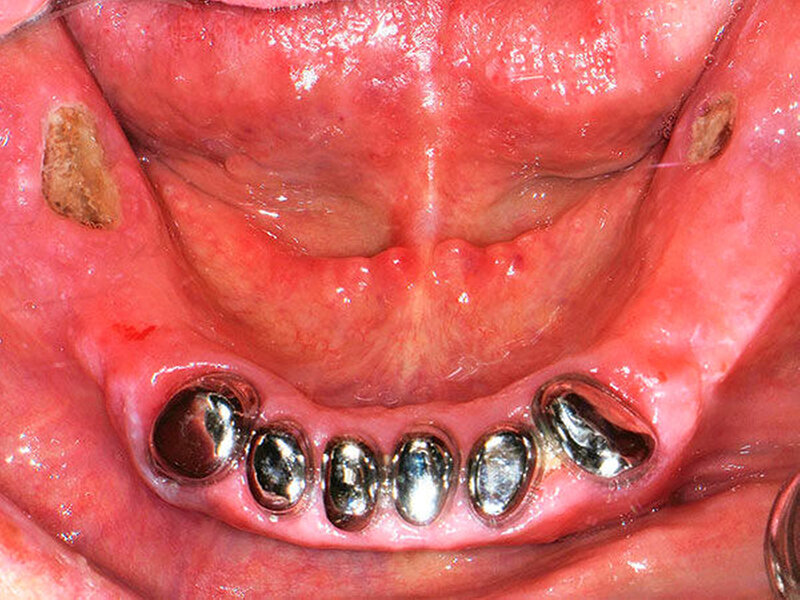

Stand heute ist aber die gründliche intraorale Inspektion noch immer der Goldstandard zur frühzeitigen Identifikation der Nekrose. Das Leitsymptom einer Medikamenten-assoziierten Kiefernekrose ist demnach der inspektorisch oder sondenpalpatorisch freiliegende Knochen [Grötz, 2012; Ruggiero, 2014]. Hierbei ist anzumerken, dass im frühen Stadium intraorale Fisteln vorliegen können, was – in Anbetracht der oben genannten Diskussion – dem inspektorisch freiliegenden Knochen gleichzusetzen ist [Grötz, 2016]. Weitere häufige Symptome sind Mundgeruch, Weichgewebsschwellungen, intra- oder extraorale Fisteln sowie Abszedierungen. Möglich sind auch eine Schädigung der Nervenfunktion (vor allem des Nervus alveolaris inferior), eine Sinusitis [Voss, 2016] sowie pathologische Frakturen des Unterkiefers [Otto, 2009]. Zusätzlich treten in vielen Fällen ausgeprägte Schmerzen auf. Diese sind jedoch kein direktes Symptom, sondern vielmehr die Konsequenz einer stattfindenden (Super-) Infektion der Nekrose [Grötz, 2016].

Das inspektable Erscheinungsbild variiert stark von kleinen sondierbaren Fistelungen bis zu großflächigen Mundschleimhautdefekten. Bei bereits freiliegendem Knochen, stellt sich dieser meist als gelblich, gräulich bis hin zu grünlich verfärbt (mit vergrößerter Porosität) und häufig aufgeweichter Struktur dar. Möglich sind ebenfalls eitriger Ausfluss (auf der Basis einer Superinfektion) und in manchen Fällen gelockerte Knochenanteile im Sinne eines Knochen-Sequesters.